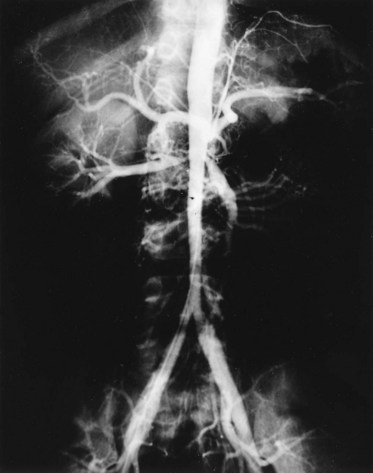

The middle aortic syndrome is a rare disorder, occurring in children or young adults, characterized by nonspecific stenosing arteritis affecting the aorta and its major branches, including the renal arteries (Fig. 39–19). This is thought to be a form of Takayasu disease, and an autoimmune pathogenesis is suspected (Kaufman, 1973). This disease can extensively involve the subdiaphragmatic aorta or, in some cases, may spare the aorta and involve primarily the renal or splanchnic vessels. The natural history is not well understood because most cases are diagnosed when the disease has already resulted in significant renal arterial stenosis in young good-risk patients, thus necessitating early revascularization. Because the inflammatory process generally does not extend to involve the iliac arteries, renal autotransplantation is the surgical treatment of choice.